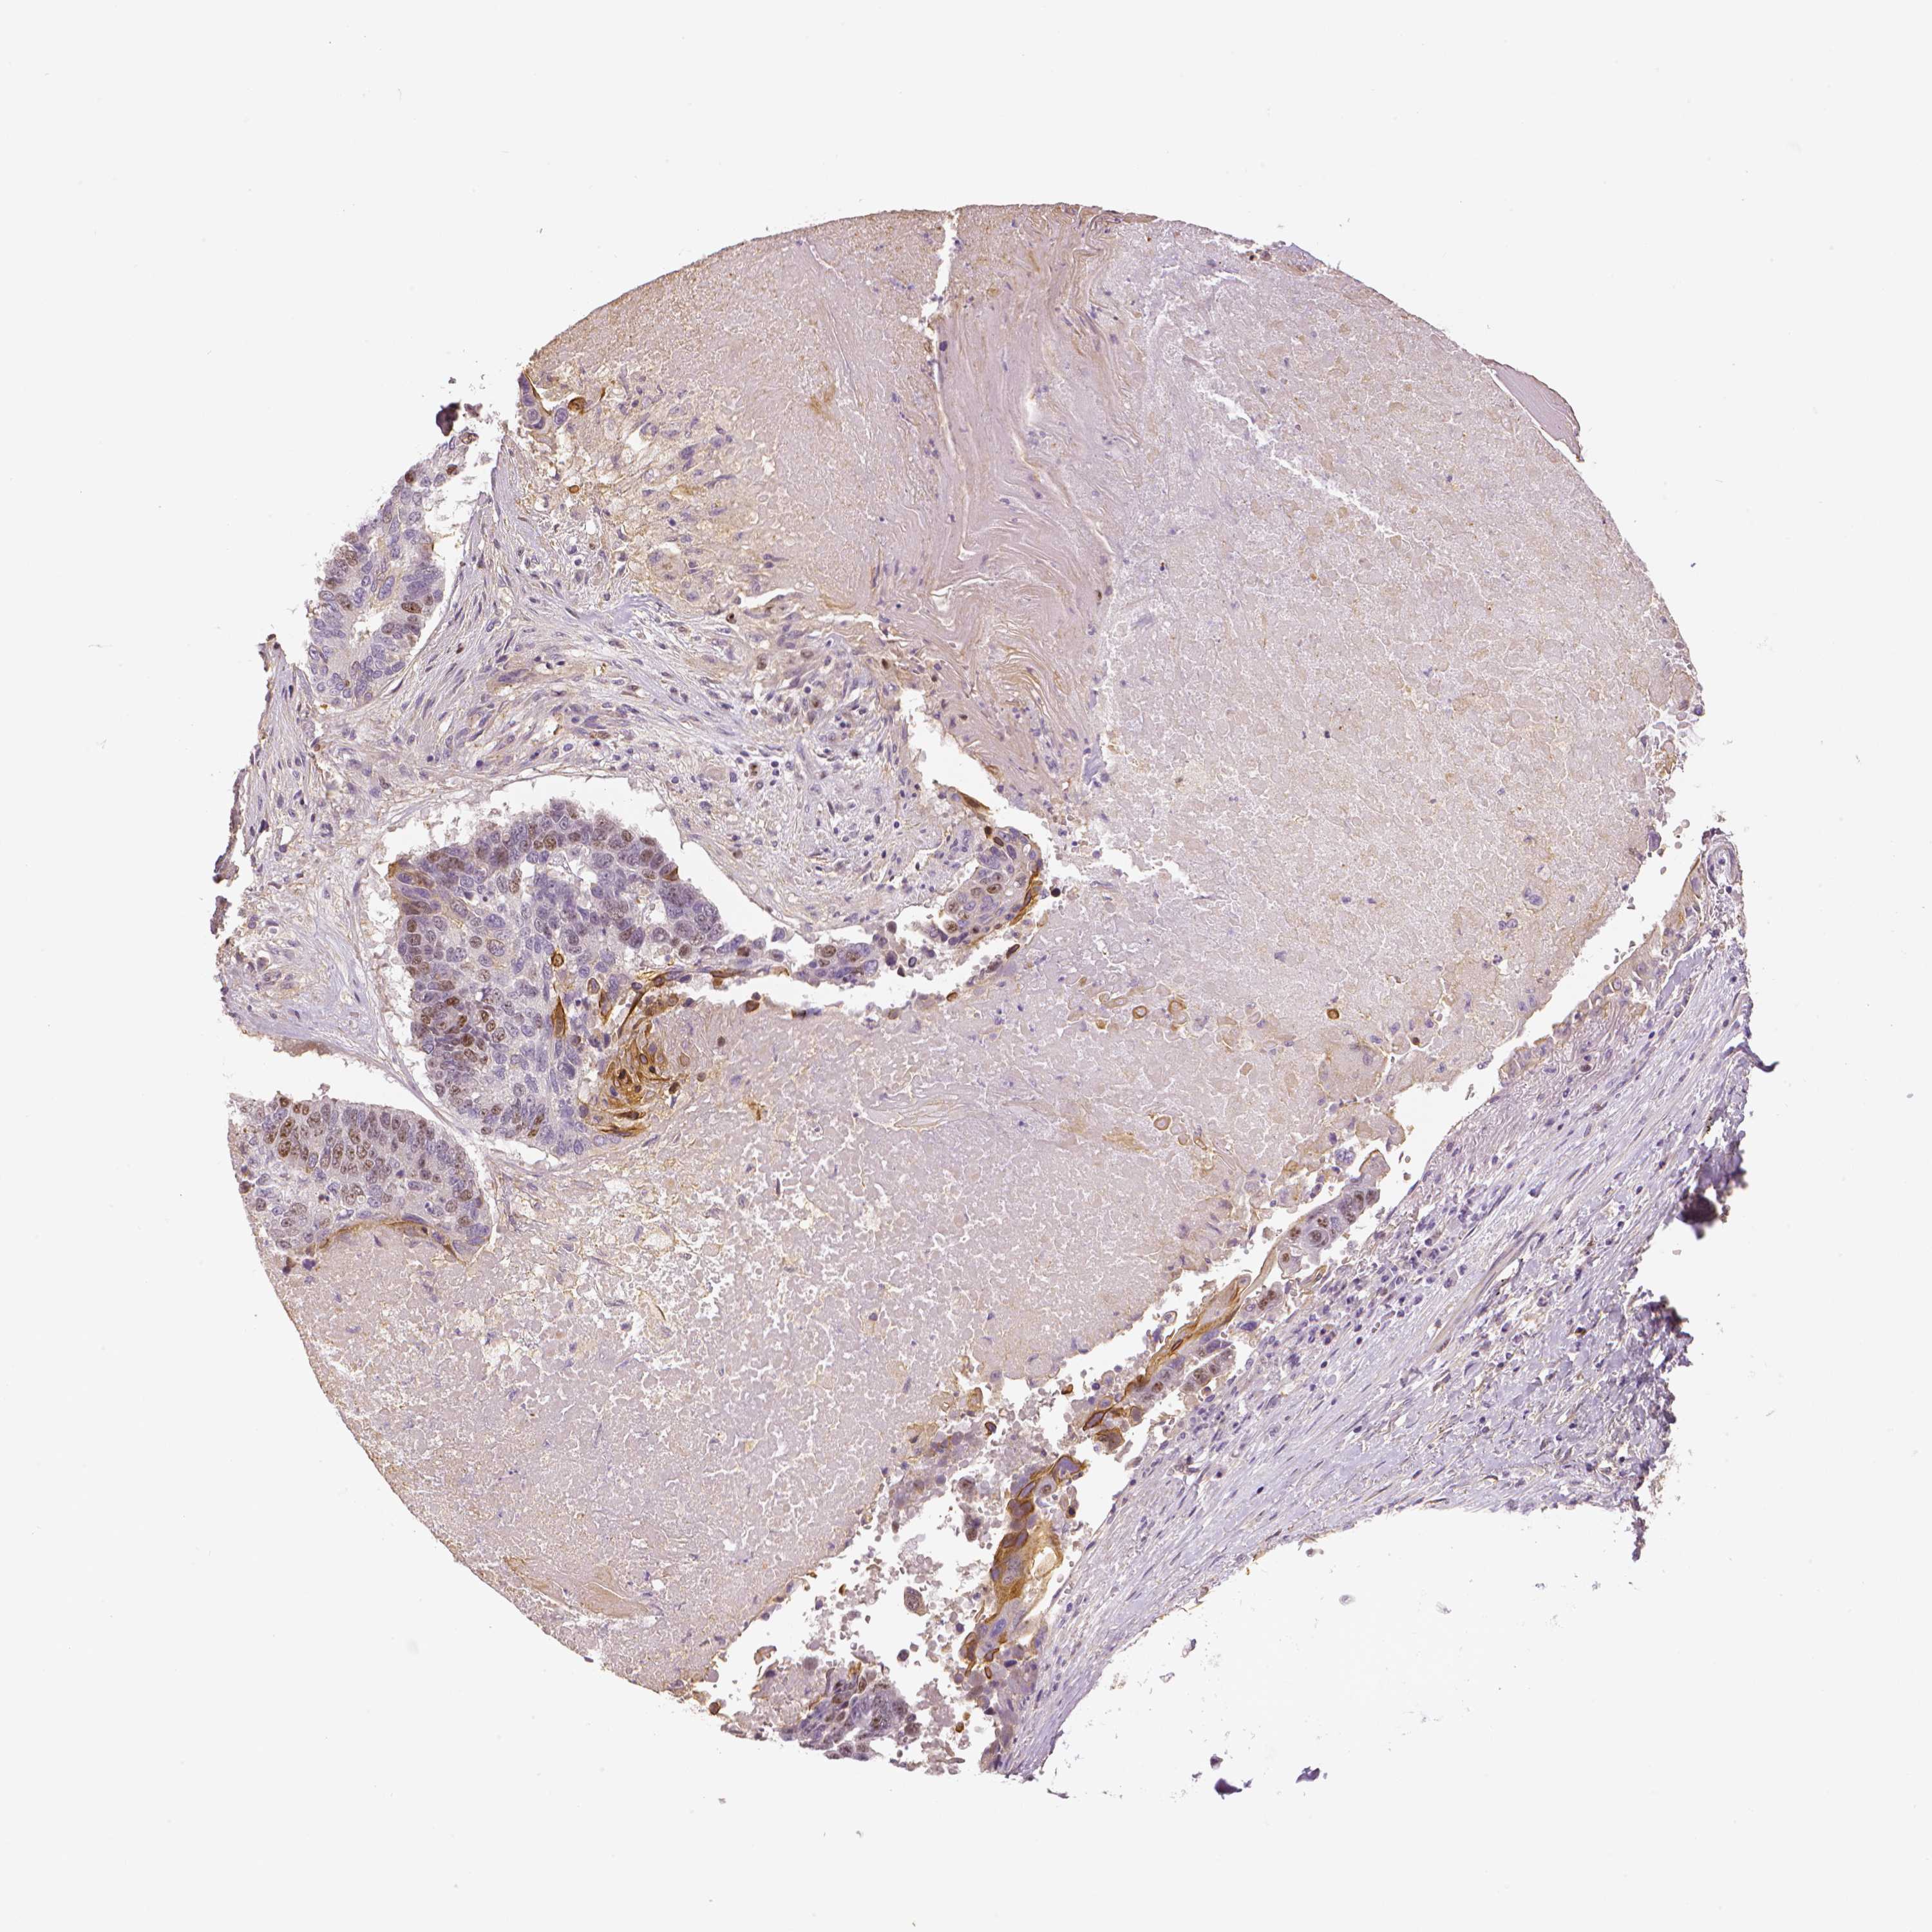

CANCER LUNG CANCER Show tissue menu

LUAD TCGA LUAD VALIDATION LUSC TCGA LUSC VALIDATION PROTEIN LUAD CPTAC PROTEIN LUSC CPTAC PROTEIN EXPRESSION

MKI67 is validated prognostic, high expression is unfavorable in Lung Adenocarcinoma (TCGA)